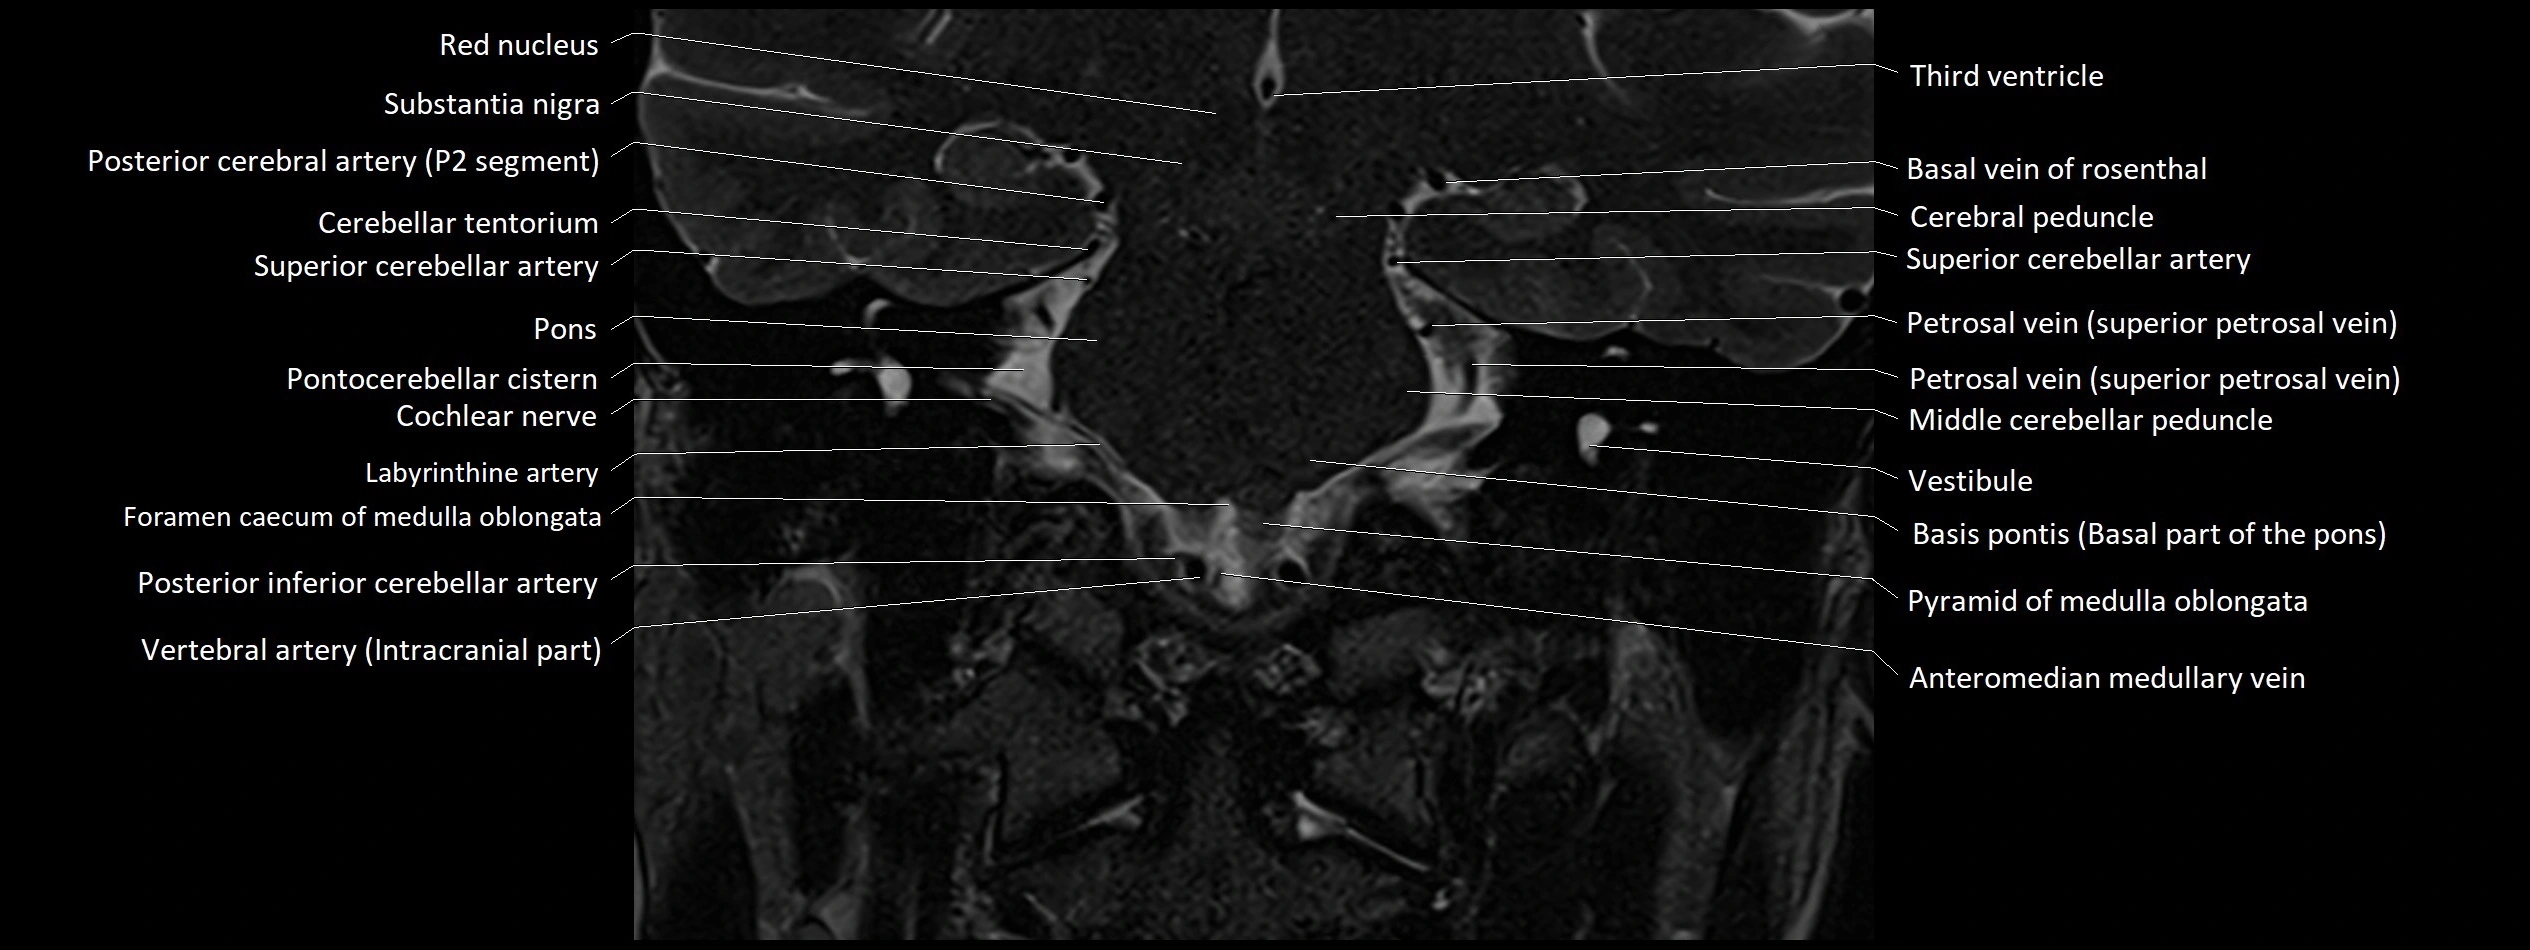

MRI images